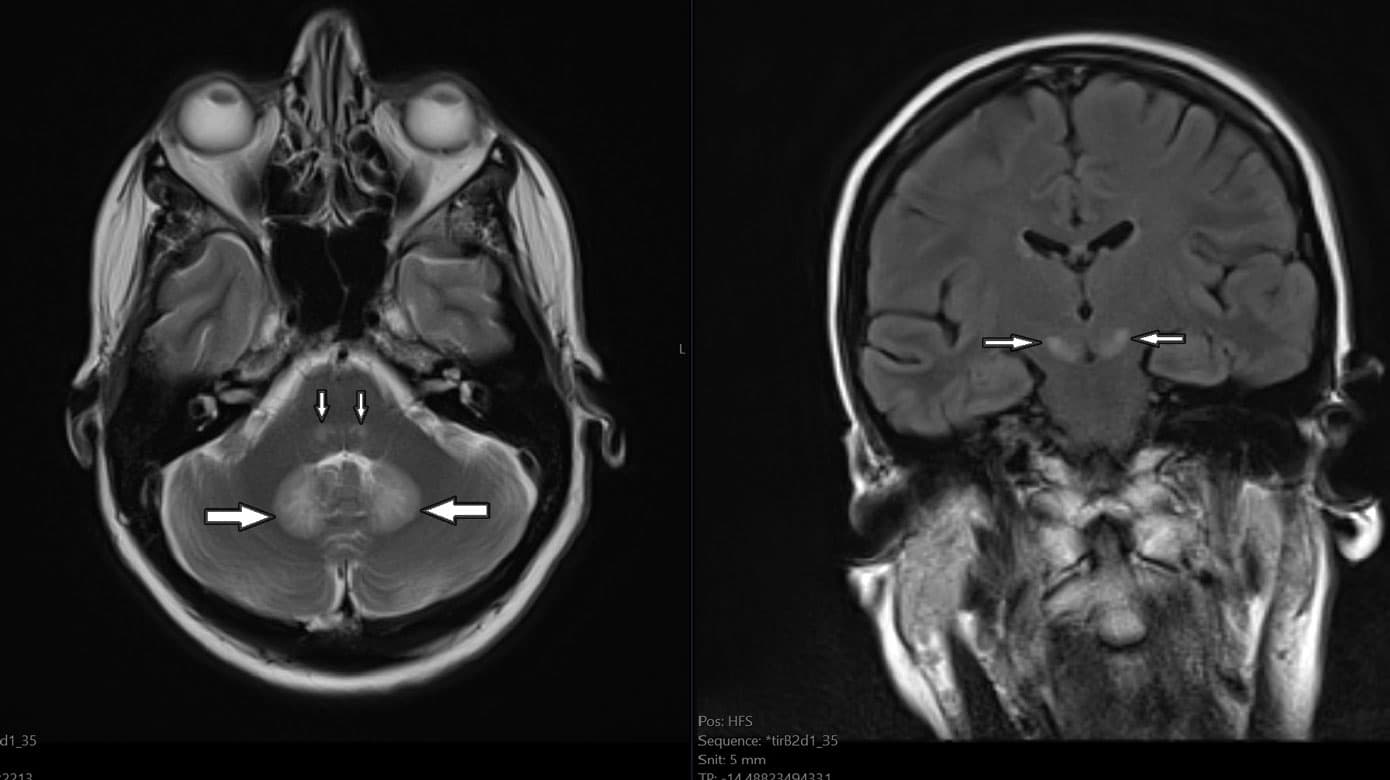

Blodprøver, inkl. paraneoplastiske antistoffer og levertal, var normale og bloddyrkning var uden vækst. Neurofysiologi viste aksonal sensorisk polyneuropati med fravær af sensoriske signaler i n. suralis og n. peroneus bilateralt og nedsat amplitude i venstre n. medianus og n. radialis. Cerebrospinalvæske viste normalt celletal, protein og laktat. BioFire-panel var negativt, herpes simplex-virus- og varicella-zoster-virus-intratekal test var negativ, og cytologisk cerebrospinalvæskeundersøgelse viste intet malignitetssuspekt. CT af cerebrum med kontrast viste intet abnormt, specielt ingen tegn på intrakraniel indvækst af primærtumor. MR-skanning af cerebrum viste fund som beskrevet i Figur 1 A + B. Et identisk MR-billede er velbeskrevet ved metronidazolinduceret encefalopati.

Baseret på det kliniske billede og radiologiske fund (Figur 1) blev toksisk encefalopati forårsaget af NI vurderet som den mest sandsynlige diagnose, og behandlingen blev seponeret. Alle radiologiske fund remitterede fuldstændigt inden for fire uger efter ophør med NI, bekræftet ved en opfølgende normaliseret MR-skanning af cerebrum. De kliniske centralnervesystem (CNS)-symptomer remitterede i samme periode, hvorimod den perifere neuropati, mere sandsynligt forårsaget af cisplatin end NI, persisterede.